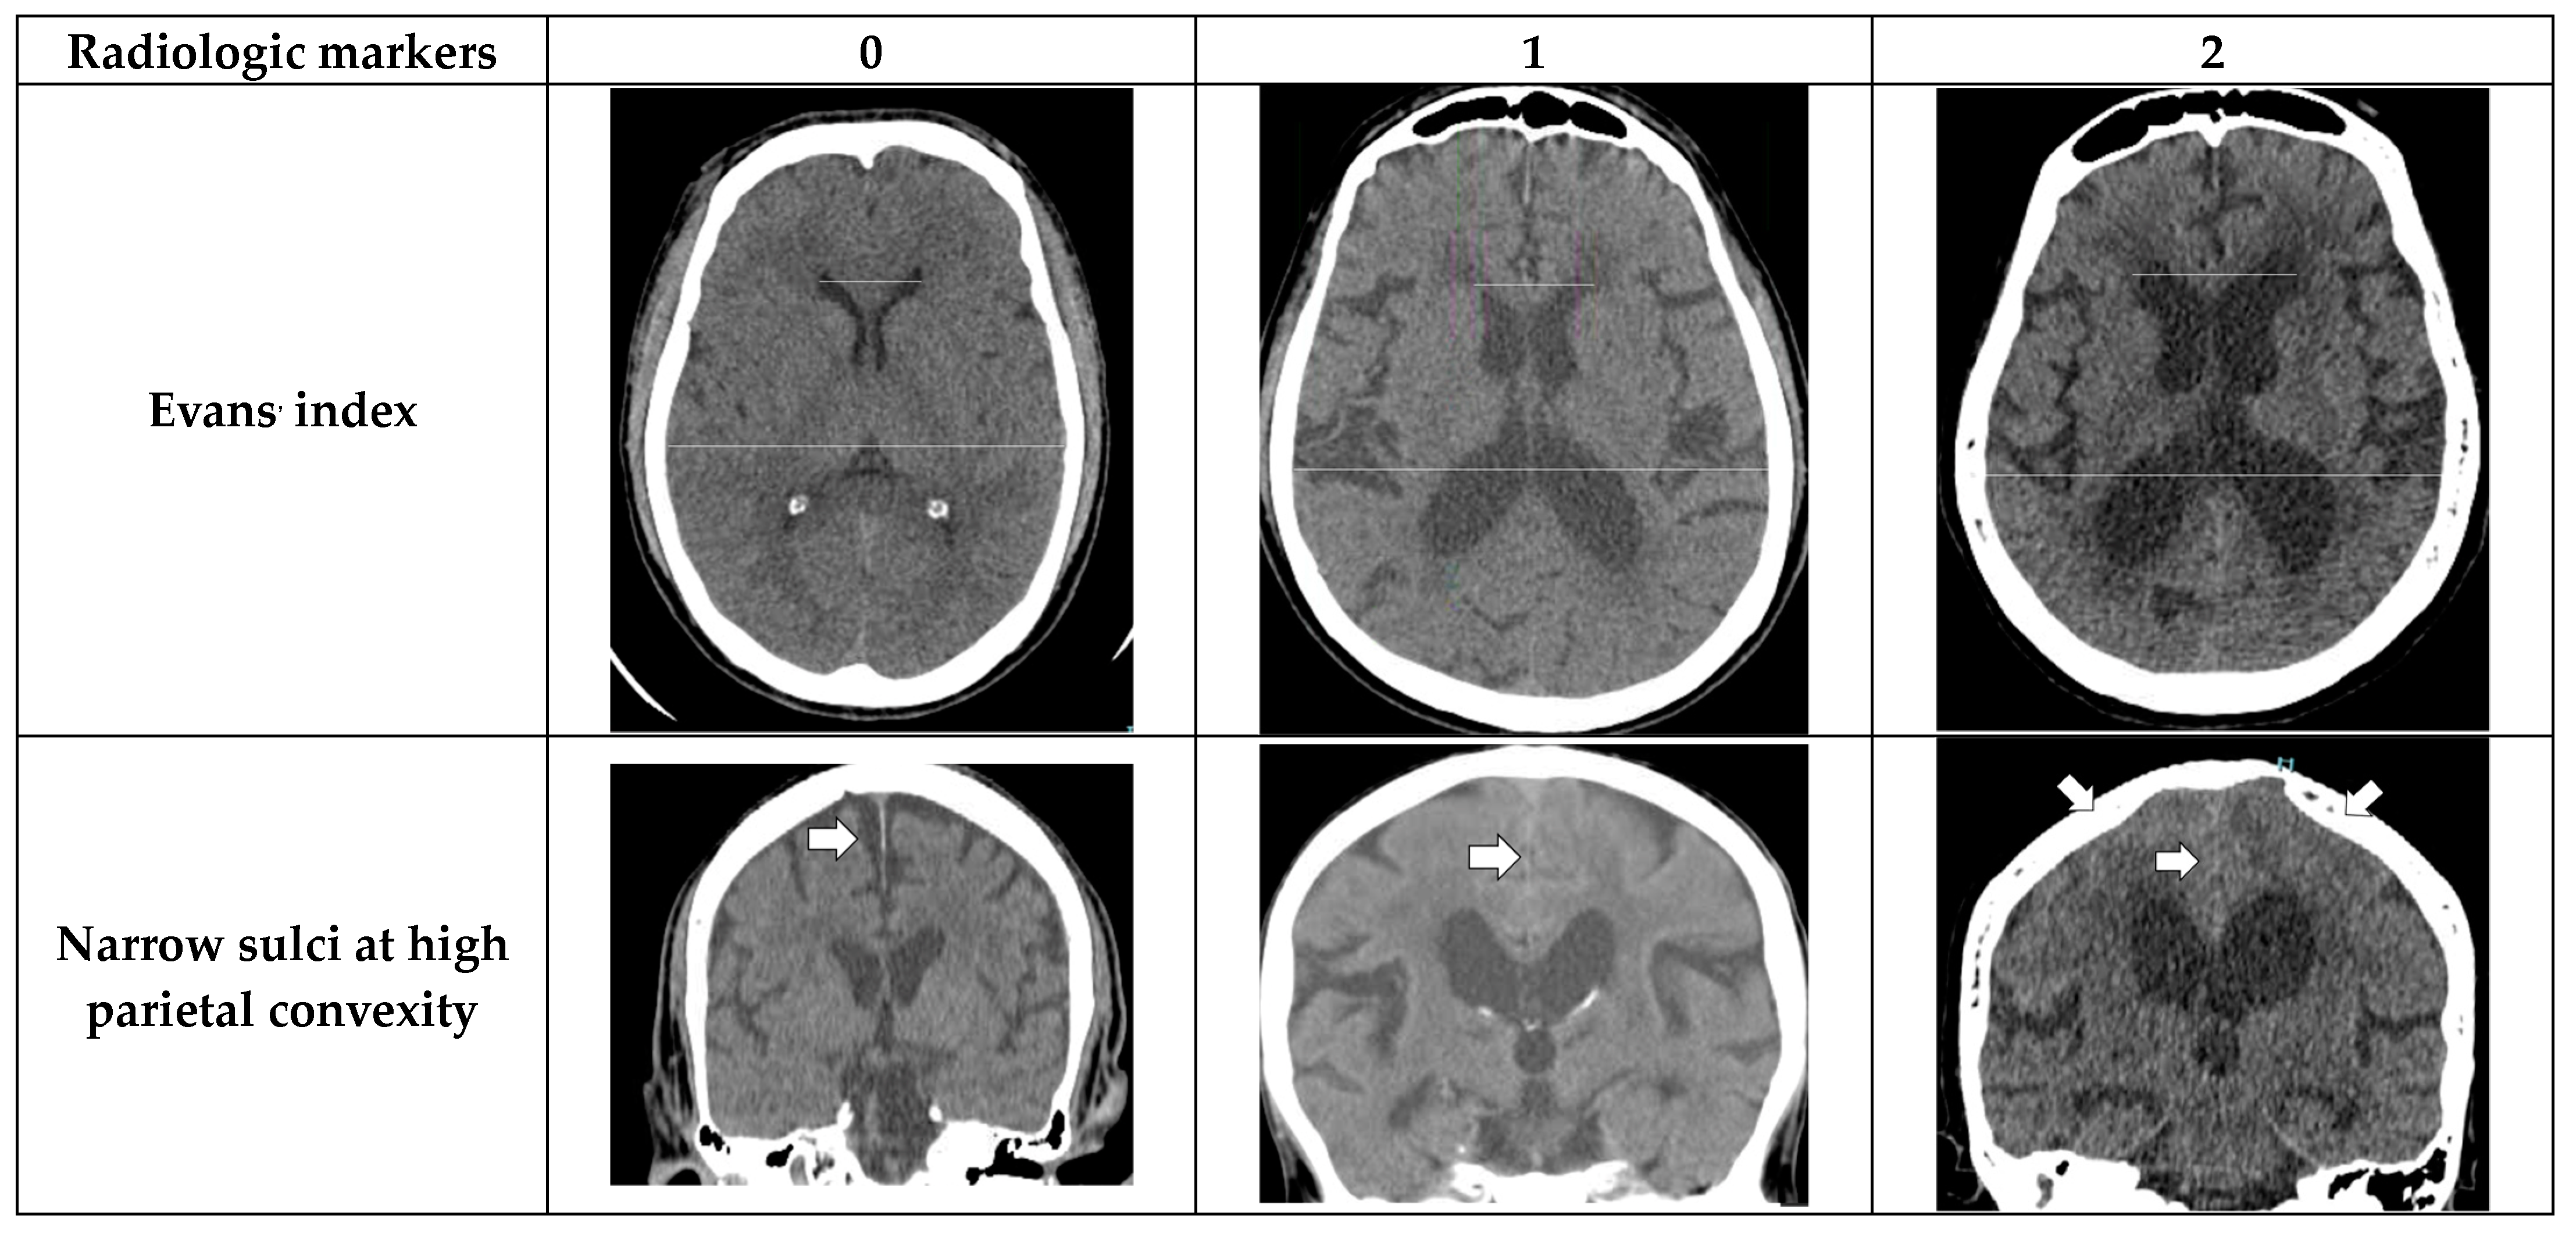

- Evans’ index: The ratio between the maximal width of the frontal horns of the lateral ventricles (B–C) by the maximal width of the inner table of the cranium in the same axial image [9].

- Narrow parietal sulci: At high-convexity and parafalcine region assessed in both axial planes in the most superior slices and coronal plane [10].

- Dilation of the Sylvian fissures: Reported as present or not present in the coronal plane compared with surrounding sulci [11].

- Focally enlarged sulci: Compared with surrounding sulci, usually found in coronal or axial planes [12].

- Temporal horns: Reported as mean width of the right and left side, measuring in the axial plane [11].

- Callosal angle: Angle between the lateral ventricles in the coronal plane through the posterior commissure perpendicular to the intercommissural plane [13].

- Periventricular hypodensities: Along the lateral ventricles graded as not present, present as a cap around frontal horns or confluently extending around the lateral ventricles [14].